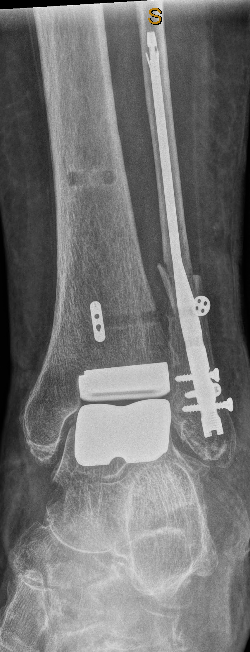

Modern Total Ankle Replacement (TAR) — also called total ankle arthroplasty — is now a well-established treatment for end-stage ankle arthritis. Contemporary research shows strong improvements in pain, walking ability and overall quality of life.